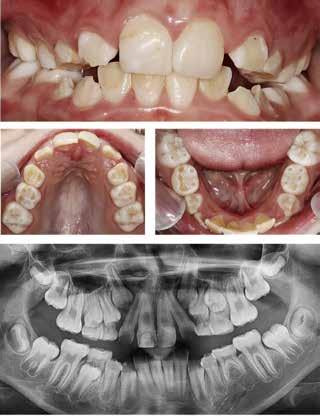

ABSTRACT

BAGGRUND – Denne kasuistik beskriver en patient, hvor der blev valgt protetisk behandling i ung alder.

PATIENTTILFÆLDE – En niårig pige havde stort behandlingsbehov og smerter fra tænderne på grund af tandudviklingsforstyrrelse. Der var flere gange forsøgt restaurering med komposit, som ikke fungerede. Laminater i feldspatkeram blev valgt for at fjerne mindst mulig tandsubstans, øge holdbarheden på restaureringerne og forbedre æstetikken. Patientens motivation, meninger og kooperationsevne var vigtige for behandlingsvalget, da behandlingen var tidkrævende og til tider udmattende for en ung patient.

KONKLUSION – Resultatet var vellykket og medførte forbedret livskvalitet. Protetisk behandling med adhæsiv teknik kan være et godt behandlingsalternativ for børn og unge på ret indikation.

EMNEORD Adhesives | amelogenesis imperfecta | ceramics | pediatric dentistry | quality of life

Protetisk behandling med adhæsiv teknik –et alternativ i ung alder?

VED BEHOV FOR OMFATTENDE TANDRESTAURERING HOS BØRN OG UNGE kan flere behandlingsalternativer være aktuelle (1). Restaurering med fyldningsmaterialer er som regel førstevalg, men i nogle tilfælde fungerer dette ikke godt nok. Ved udarbejdelse af behandlingsplan må klinikerne kende til mulige behandlingsalternativer og vurdere disse på baggrund af kliniske fund, patientens symptomer og kooperationsevne samt patientens ønsker og planlægge behandling i et livsløbsperspektiv.

PATIENTTILFÆLDE

Beskrivelse af patienten Patienten blev henvist til specialistuddannelsen i pædodonti ved Universitetet i Oslo, da hun var syv år gammel, for diagnostik og behandling af tandudviklingsforstyrrelse i primære og permanente tandsæt. Pigen havde pollenallergi, var ellers sund og rask og havde intet medicinforbrug.

Klinisk undersøgelse viste emaljehypoplasier og hypomineralisering på 1+, +1, 2-, 1-, -1 og -2 (Fig.1). Hun havde Angle klasse II, pladsmangel i begge kæber og agenesi af -5. Der var isninger ved spisning og tandbørstning. Fundene var forenelige